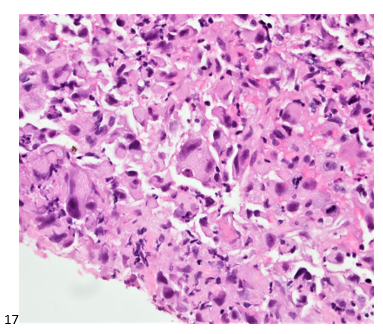

P.S. Sometimes diving and cytology overlap under the microscope, too!